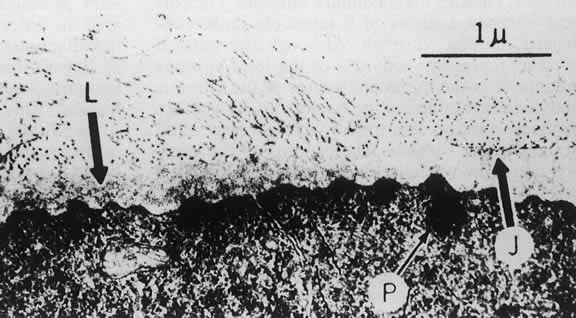

The nature of the adhesion between the vitreous cortex and the ILM is enigmatic. This adhesion is strongest at the optic nerve, the macula, the vitreous base, and retinal vessels. Foos6 demonstrated attachment plaques between Müller's cell cytoplasm and the ILM in the basal and equatorial retina (Fig. 2). Vitreous traction mediated by vitreous fibrils may contribute to these adhesions. These attachment plaques are not present posterior to the equator except where the ILM is thinned in the fovea. This anatomic variation in the fovea region may play a role in the pathogenesis of some of the vitreomacular disorders.

The ILM also thins over major blood vessels. Vitreous strands extend through pores in the ILM to surround the vessels11 and have been termed vitreoretinovascular bands.12 These bands may explain the strong adhesion between the vitreous and retinal vessels.

In the vitreous base, collagen fibers are relatively coarse, are numerous, and insert perpendicularly to the retina and pars plana. These fibers consist of collagen fibrils with diameters of 10.8 to 12.4 nm.16 The microscopic detail of the vitreous fibers attachment to the vitreous base varies from anterior to posterior. Anterior to the ora the fibers are less dense than posterior to the ora. Electron microscopic studies by Gartner17 demonstrate that the vitreous fibers have complex interdigitations with the reticular fibrillar materials of the basement membrane of the nonpigmented ciliary epithelium but do not pass between the cells. The anteriormost fibers splay out anteriorly to form the anterior loop of the vitreous base, which is important in the pathogenesis of anterior PVR.18 Posterior to the ora, bundles of vitreous fibrils attach to the ILM. Cords of vitreous collagen insert into gaps between the neuroglia. Gloor and Daicker19 likened this arrangement to Velcro and suggested that this may explain the strong vitreoretinal adhesion of the vitreous base. Cellular elements are also present in the vitreous base. Fibroblast-like cells are present anterior to the ora, and macrophage-like cells are posterior to the ora.17 These cells may play a role in the hypocellular gel contraction that characterizes anterior PVR.